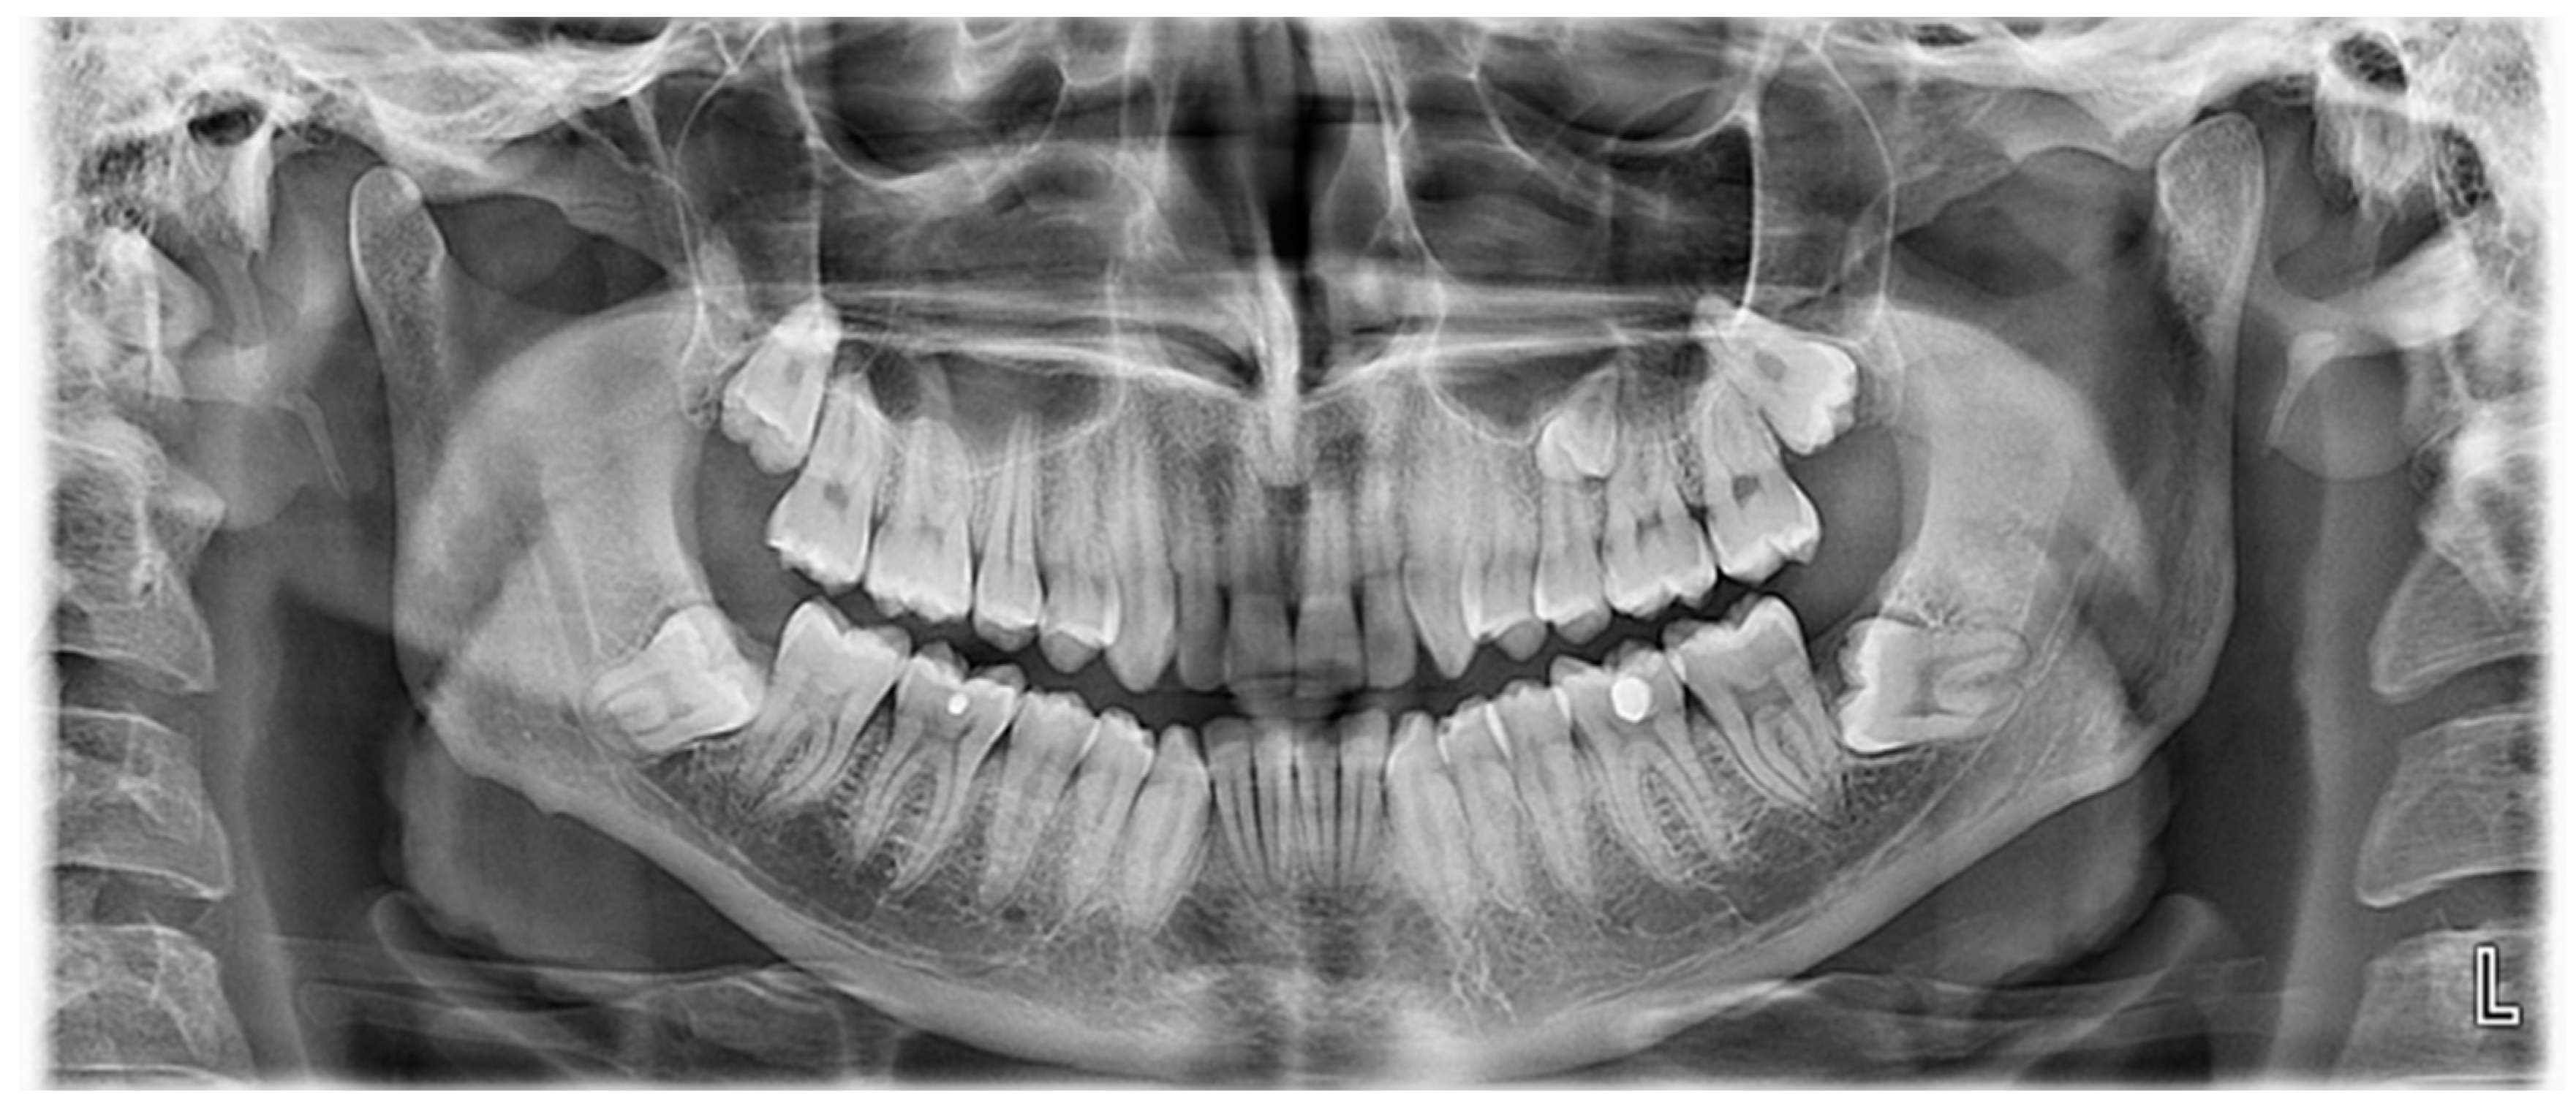

2.1. Case 1

Case 1 Presentation